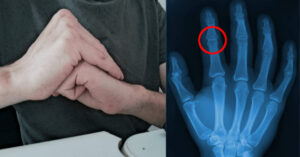

Cosa accade quando si “scrocchiano” le dita? Ecco la verità!

Forse lo fai semplicemente come un gesto abitudinario o per riscaldarti prima di un allenamento. In realtà è qualcosa che abbiamo fatto tutti almeno una…